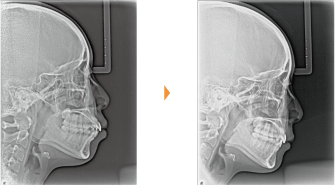

| 主訴 | 前歯の隙間が気になる |

| 年齢・性別 | 42歳 / 女性 |

| 治療方針 | 咬合力により上顎前歯が前方に傾斜したと思われるケース。元に戻りやすいため過蓋咬合をしっかり治して、保定には固定式のリテーナーも併用する。 |

| 抜歯部位 | 非抜歯 |

| 使用装置 | マルチブラケット装置 |

| 治療期間 | 16か月 |

| リテーナー | 上顎インビジブル、フィックス、下顎インビジブル |

| 費用 | 765,000円(税別) |